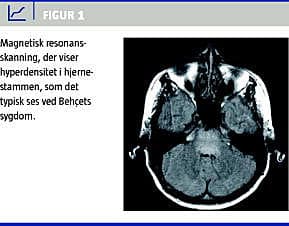

En tidligere rask 38-årig kaukasid dansk kvinde blev i januar 2004 indlagt på neurologisk afdeling med bankende hovedpine, dobbeltsyn, kvalme, opkastninger og gangbesvær. Der fandtes hypæstesi og diskret parese af venstresidige ekstremiteter. I cerebrospinalvæske (CSF) var der 110 overvejende mononukleære celler pr. mikroliter og spinalprotein på 0,67 g/l; og ingen antistoffer mod borrelia, syfilis, herpes simplex, varicella zoster eller cytomegalovirus (CMV). Serum-angiotensinkonverterende enzym (ACE) og forskellige autoantistoffer var negative. Magnetisk resonans (MR)-skanning af cerebrum viste øget signalintensitet i pons og medulla oblongata (Figur 1 ). De neurologiske symptomer forsvandt hurtigt på metylprednisolon 1 g intravenøst i tre dage, og ny MR-skanning viste regression af forandringerne.